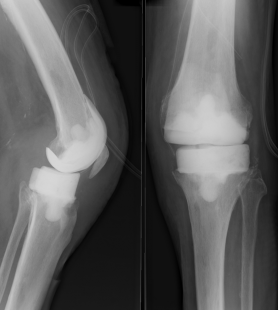

Plusieurs gestes chirurgicaux peuvent être envisagés, le choix se fondant sur de très nombreux paramètres. Le lavage/drainage peut suffire dans des infections récentes. Mais souvent, il est complété par l'ablation de la prothèse et de tous les dispositifs implantés (ostéosynthèse, ciment), en raison de la présence d'un biofilm à la surface des implants. « Il s'agit d'une opération complexe, longue, hémorragique, qui peut être réalisée en un ou deux temps opératoires, rapporte le Pr Bizot. Le remplacement en un temps n'est indiqué que si l'on a la certitude que le nettoyage est complet et que le patient peut supporter une intervention longue ». La chirurgie en deux temps différencie le nettoyage (avec l'ablation de la prothèse), et la repose d'une nouvelle prothèse. Elle permet de faire des prélèvements profonds afin d'identifier formellement le ou les germes en cause, d'apprécier les conditions locales, d'anticiper les difficultés de la repose, et ainsi de choisir le type de la nouvelle prothèse. Un espaceur (ou entretoise) est en général mis en place pour 4 à 6 semaines avant la seconde opération, qui consiste en un nouveau lavage et la pose d'une nouvelle prothèse. Le recours à un ciment acrylique contenant de la gentamicine libérée localement peut être utile. « Le geste en deux temps donne en théorie plus de sécurité sur le plan sceptique, mais il implique deux hospitalisations, deux anesthésies et de l'inconfort pour le patient entre les deux opérations, souligne le Pr Bizot. La tendance actuelle est de privilégier le changement de prothèse en un temps, mais de nombreux paramètres rentrent en compte, liés au patient, aux conditions locales, au type de germe, mais aussi aux convictions du chirurgien ».

« Tous les patients ne seront pas guéris, même dans les centres de référence, et les patients doivent en être informés, insiste le Pr Bizot. Nous ne disposons pas d'un registre national très nourri des prothèses, mais les données de la littérature internationale rapportent des taux de guérison compris entre 80 et 90 %, après changement de prothèse, sans différence significative entre le « un temps » et le « deux temps ». L'infection sur prothèse reste une complication grave. La chirurgie, souvent lourde, réclame un opérateur entraîné, et s'accompagne d'une morbidité élevée ».